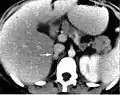

КТ живота: феохромоцитома.